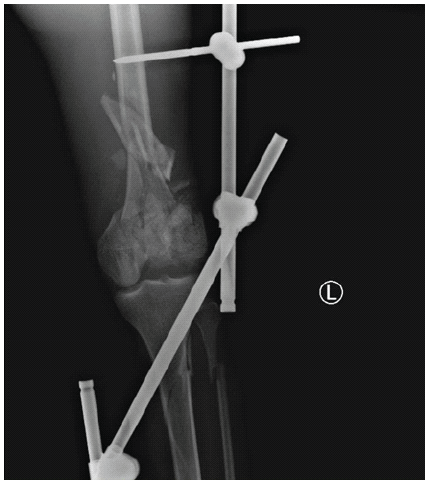

A medically free 25-year-old male smoker was brought to the emergency department by paramedics following a motor vehicle accident. The patient was conscious, alert, and oriented. The primary survey was unremarkable. On secondary survey, he had a left knee wound and deformity, as well as swelling and deformity of the right ankle. Imaging revealed mild bilateral pneumothorax, pulmonary contusions, and a comminuted fracture of the left iliac crest. Portable X-rays showed an open comminuted left distal femur and shaft fracture with intra-articular extension (AO 33-C3), a right talar neck fracture (Hawkins I), and a right distal tibial fracture with intra-articular extension (AO 43-C). The right foot and ankle injuries were managed conservatively with closed reduction and slab immobilization. The left femoral fracture was treated acutely with irrigation, debridement, and a knee-spanning external fixator (Fig. 4).

Figure 4: Radiographs showing comminuted distal femur fracture treated initially with a knee-spanning external fixator.

First and second surgeries involved combined medial and lateral exposure with tibial tubercle osteotomy, partial fixation of the medial condyle using a distal femoral plate, and insertion of a cement spacer. The lateral condyle was non-reconstructible. The second operation focused on revising fixation, correcting deformities, and reinserting a cement spacer into the bone defect of the distal femur in preparation for DFR (Fig. 5).

Figure 5: Interim reconstruction with partial fixation of the medial femoral condyle and placement of a cement spacer in the distal femoral defect.